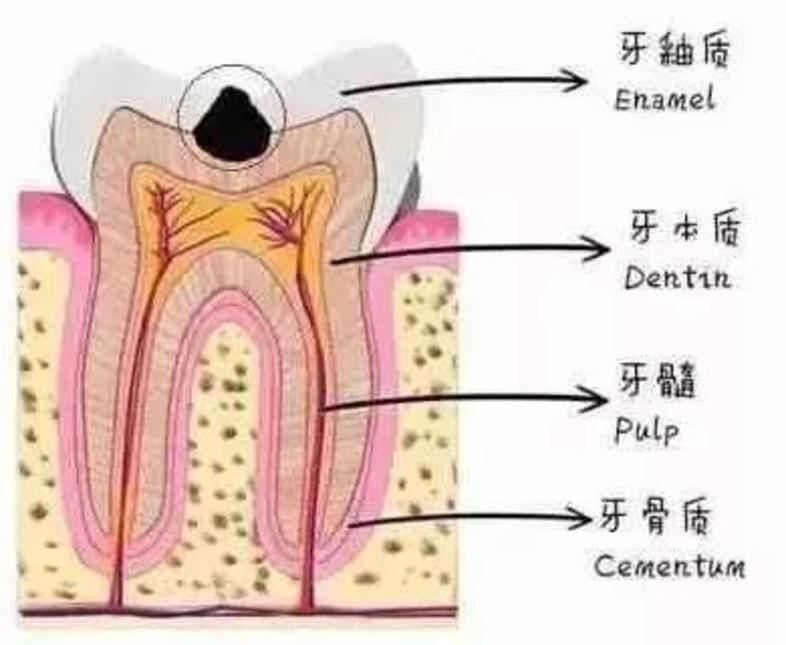

牙齿分为三层,最外层坚硬的牙釉质,不会感觉到疼痛;中间的牙本质能够感受到疼痛;最里层是敏感的牙神经,一受刺激便会疼痛难忍。

浅龋齿:细菌到达牙釉质层,患者没有明显感觉

中龋齿:细菌到达牙本质,一开始会感觉酸痛,一段时间后酸痛感就会消失

深层龋齿:细菌到达牙本质深层,接近牙髓,咬东西时会感到刺痛,疼痛感会反复出现.

牙髓炎:细菌进入牙神经,患者会有剧烈的疼痛感。如果不及时治疗,细菌会杀死牙神经

运气不好的话,它可能是这样子的↓↓